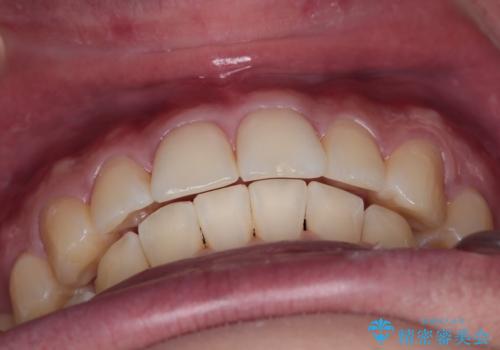

【インビザライン】短期間で出っ歯を治したい

- 出っ歯と口元の突出感が気になるということで来院されました。抜歯矯正も考えられますが、今回は早く終わらせたいという要望があり非抜歯での治療にしました。また遠方から来院されているため、来院回数のおさえられるインビザラインを選択しました。

非抜歯での治療のため、今回はスペース確保のために遠心移動とおもにIPRの処置を取り入れました。